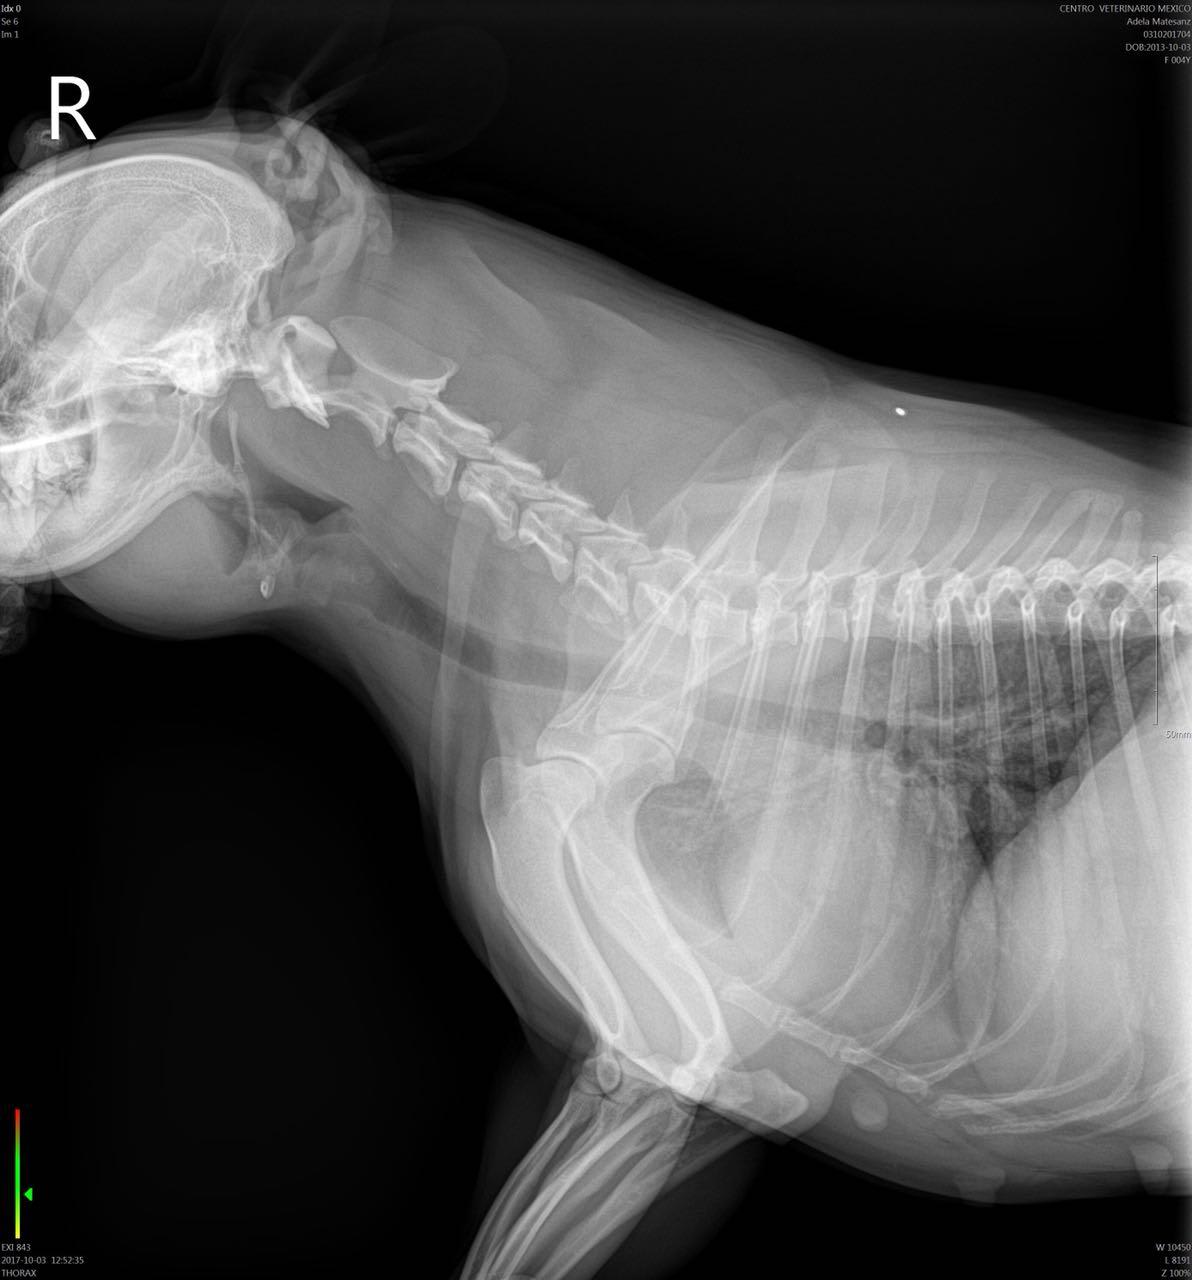

Hello, my dog was chewing on a pork rib bone yesterday and i think i got most of it out, she's a 4 year old french bulldog not spayed, i gave her a slice of bread right after soaked in olive oil and she puked it, took her to the vet they got xrays she was hacking and coughing this morning the xrays dont show a blockage but she ate today and puked all her food and part of yesterdays i checked there were no bones or anything solid in the vomit, she has also been pooping fine